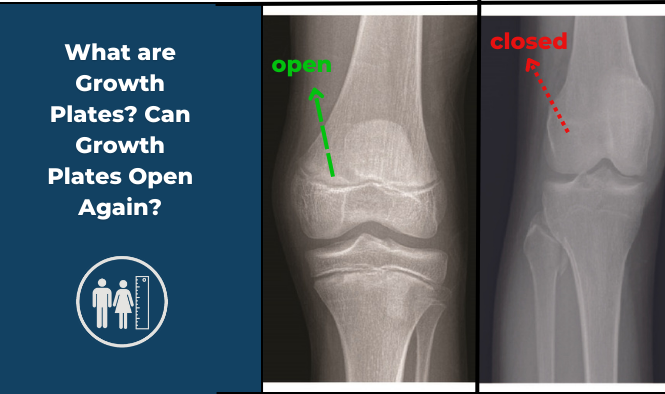

Learn about growth plates, when they close, and how they affect height. Explore limb lengthening surgery as a…